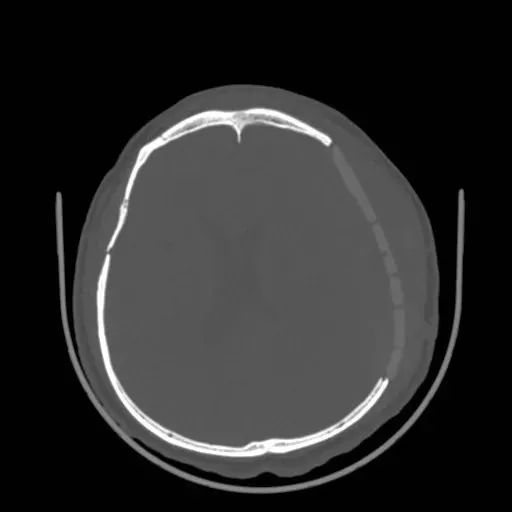

顱骨修補術前

PEEK顱骨修補產(chǎn)品通常在影像學檢查中表現(xiàn)良好,具有較好的影像兼容性。這意味著在X射線、計算機斷層掃描(CT)、磁共振成像(MRI)等醫(yī)學影像檢查中,PEEK顱骨植入物通常不會引起顯著的偽影或影響圖像的清晰度。對于患者術后復查以及其他疾病的診療有著重要的作用。

術后復查無偽影